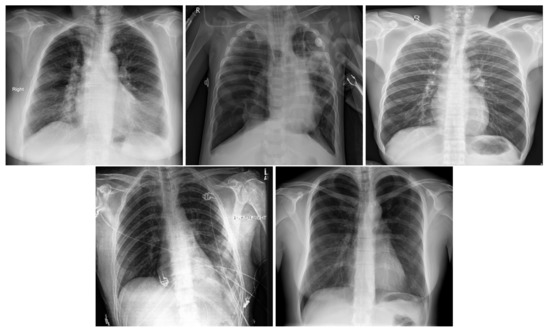

In order to distinguish between COVID-19 and the other lung diseases and healthy cases, we created a five-class COVID-19 database. In fact, COVID-19 is a viral pneumonia, so we aim to distinguish between Bacterial, Viral Pneumonia, COVID-19, and Healthy cases. In addition, we considered Lung Opacity Not Pneumonia diseases as the fifth class. Similar to the three-class COVID-19 database, we used data augmentation techniques to obtain augmented data to train our models. The same data augmentation techniques were applied for the training split to obtain 12 augmented images for each image. Table 3 summarizes the five-class COVID-19 database number of images by split and their resources. Figure 2 shows an X-ray example for each class of the five-class COVID-19 database.

Figure 2. In order: COVID-19, Viral Pneumonia, Bacterial Pneumonia, Lung Opacity, Normal.